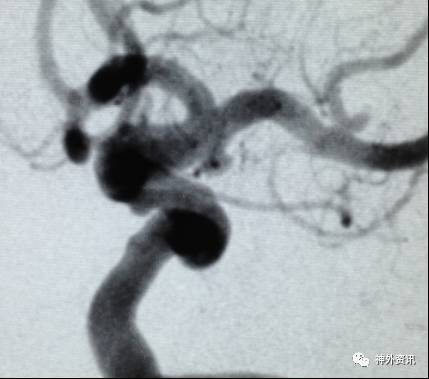

病例一

病例二

病例三

病例四

病例五

病例六

病例七